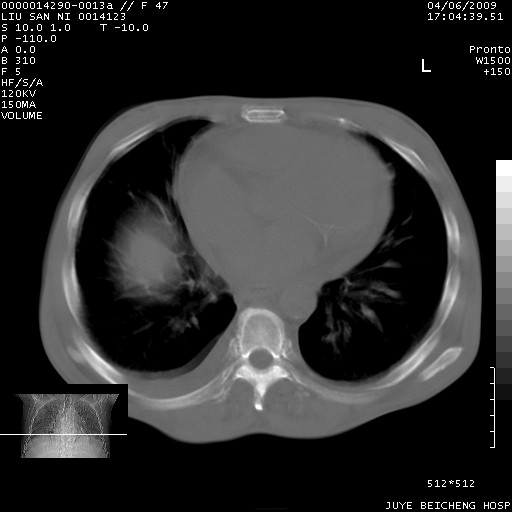

以下是引用前行在2009-4-7 10:31:00的发言:[br]肝脾肿大;双肾增大,双肾盂少量积水可能,肾膜膜增厚,肾周间隙增宽,并见桥间隔,提示结缔组系统疾病、系统性红瘢狼疮肾可能性大。继发右侧胸腔、心包、腹腔积液。